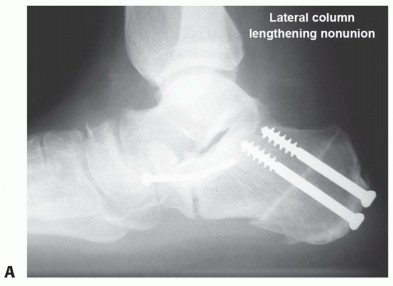

Complications

Nonunion (FIG 8) or malunion Graft fracture or displacement Painful retained deep hardware

FIG 8 • A. Radiograph of late graft nonunion and hardware failure. B. Radiograph showing healed revision with plate fixation.*